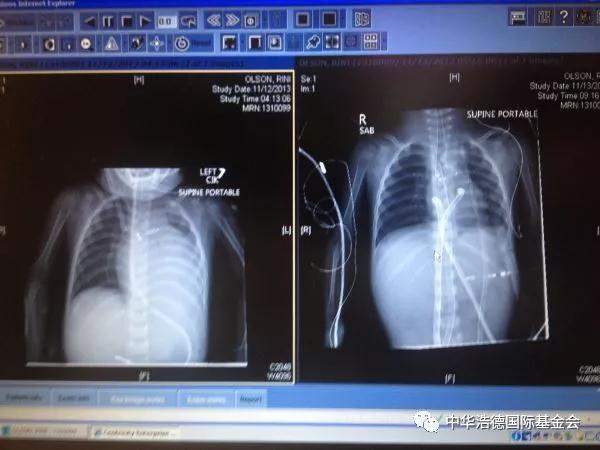

玲玲在美国的治疗也是十分艰辛,当飞机降落在美国时,玲玲就直接被送入Doernbecher儿童医院。那里心脏病科医生和护理人员告诉我们,她的心脏病到了末期,做不了手术。但是家庭都深信她离开这个世界的时间还没有到,他们不住地为她祈祷,在接下来的4周,永玲的心脏每况愈下,家庭给她的手掌和脚掌做了灰泥的印记,还请了摄影师到医院给她们家拍了一张家庭合照。这样一直到10月16日,西雅图儿童医院同意评估玲玲的心脏移植手术。她的妈妈和她搭乘救护直升飞机,到了心脏ICU。事情进展迅速,她因呼吸衰竭而接受插管治疗的当天就接纳为高危心脏移植候选人。在美国等待一个可移植的儿科心脏平均要3到5个月的时间。她上了移植名单的8天后,她第一次心搏停止,继而被接上体外膜氧合生命维持器,估计只能活3到4周。随着一天一天过去,她接连患上各种并发症。但是在11月12日星期二,也就是她上了移植手术名单的19天后,西雅图儿童医院移植医生Mike McMullen进入玲玲的房间,告诉家庭说:“有一个适合玲玲的心脏了”。当移植科医生集中在美国的某间医院,在那里一个家庭的孩子去世了,他们在悲痛中所做的选择是把玲玲从死亡的边缘中救了回来。玲玲当天晚上9点半进入手术室。家庭从心脏重症监护室的窗口看到救护车把捐给玲玲的心脏送来了。这颗心经过了两千英里的飞行终于到达目的地。当治疗小组把玲玲的治疗由体外膜氧合生命维持器转换到接受体外循环时,她的心搏刚好停止了。这是医生后来告诉家庭的。很快地,另一个家庭的宝贵孩子的心被安装在新的家,就像一个收养孩子到了新家一样。不是失去,而是希望。

玲玲的病情十分严重